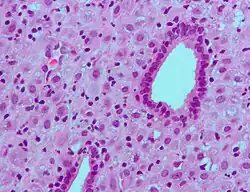

Micrograph of decidualized endometrium due to exogenous progesterone. H&E stain.

The decidua has a histologically-distinct appearance, displaying large polygonal decidual cells in the stroma. These are enlarged endometrial stromal cells, which resemble epithelium (and are referred to as "epithelioid").

Decidualization includes the process of differentiation of the spindle-shape stromal fibroblasts into the plump secretory decidual cells, which create a pericellular extracellular matrix rich in fibronectin and laminin (similar to epithelial cells).

Vascularity, as well as vascular permeability, is enhanced in the decidualizing endometrium.

Its leukocyte population is distinct, with the presence of large endometrial granular leukocytes being predominant, while polynuclear leukocytes and B cells are scant.